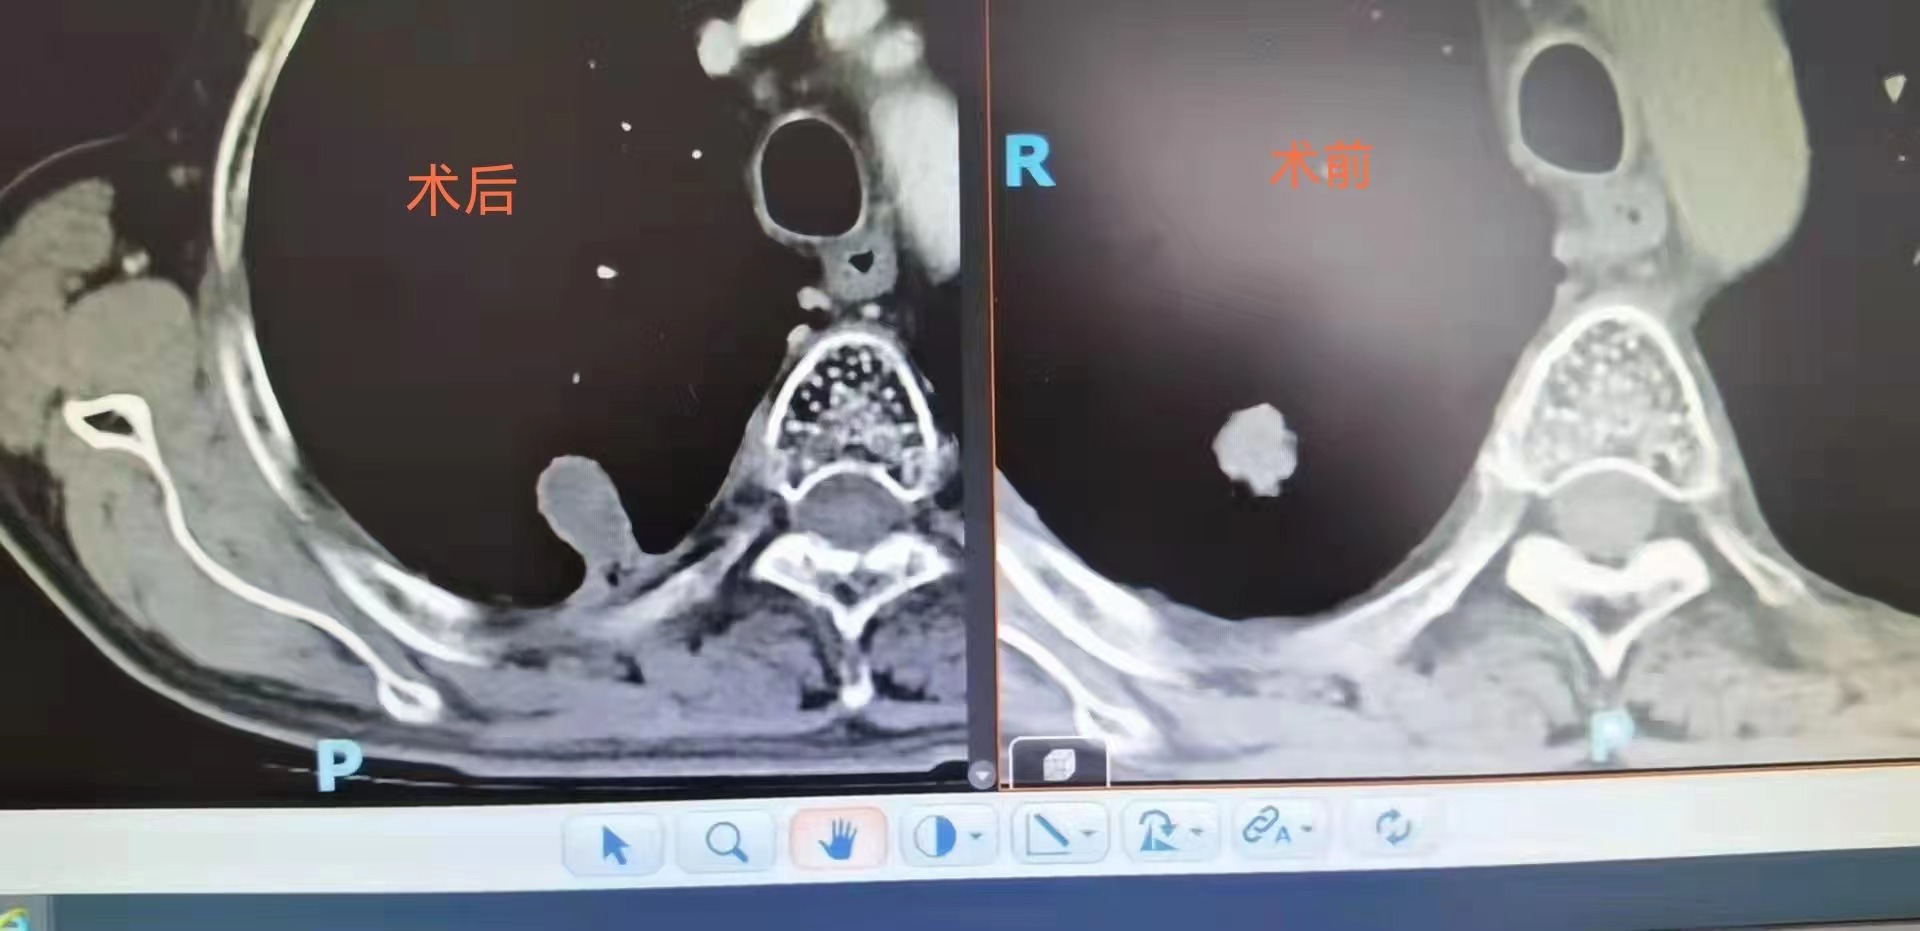

小细胞肺癌肺内转移,冷消融病灶坏死